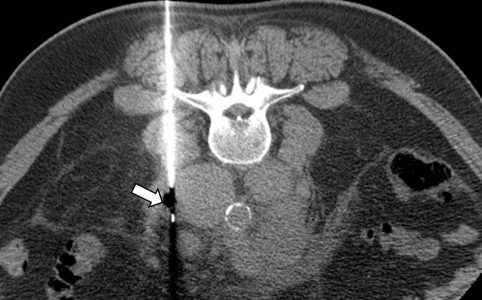

Η διαδερμική βιοψία είναι μια ελάχιστα επεμβατική μέθοδος λήψης υλικού από τον όγκο για κυτταρολογική και ιστολογική εξέταση από εστιακές αλλοιώσεις του ήπατος, του πνεύμονα, του μαστού, του νεφρού κλπ. Συνιστάται από τον κλινικό ιατρό ανάλογα με το είδος και το μέγεθος της βλάβης και πραγματοποιείται με ασφάλεια από επεμβατικό ακτινολόγο συνήθως με την καθοδήγηση αξονικού τομογράφου ή υπερήχων. Στη σύγχρονη ογκολογική θεραπεία, όπου γίνεται προσπάθεια καταπολέμησης του καρκίνου σε μοριακό επίπεδο, κρίνεται αναγκαία η ακριβής ιστολογική ταυτοποίηση του όγκου, ώστε να εφαρμοσθεί εξατομικευμένη θεραπεία για το βέλτιστο αποτέλεσμα.

Διαδερμικά κατευθυνόμενη βιοψία αδενοκαρκινώματος πνεύμονα

Ακτινολογία